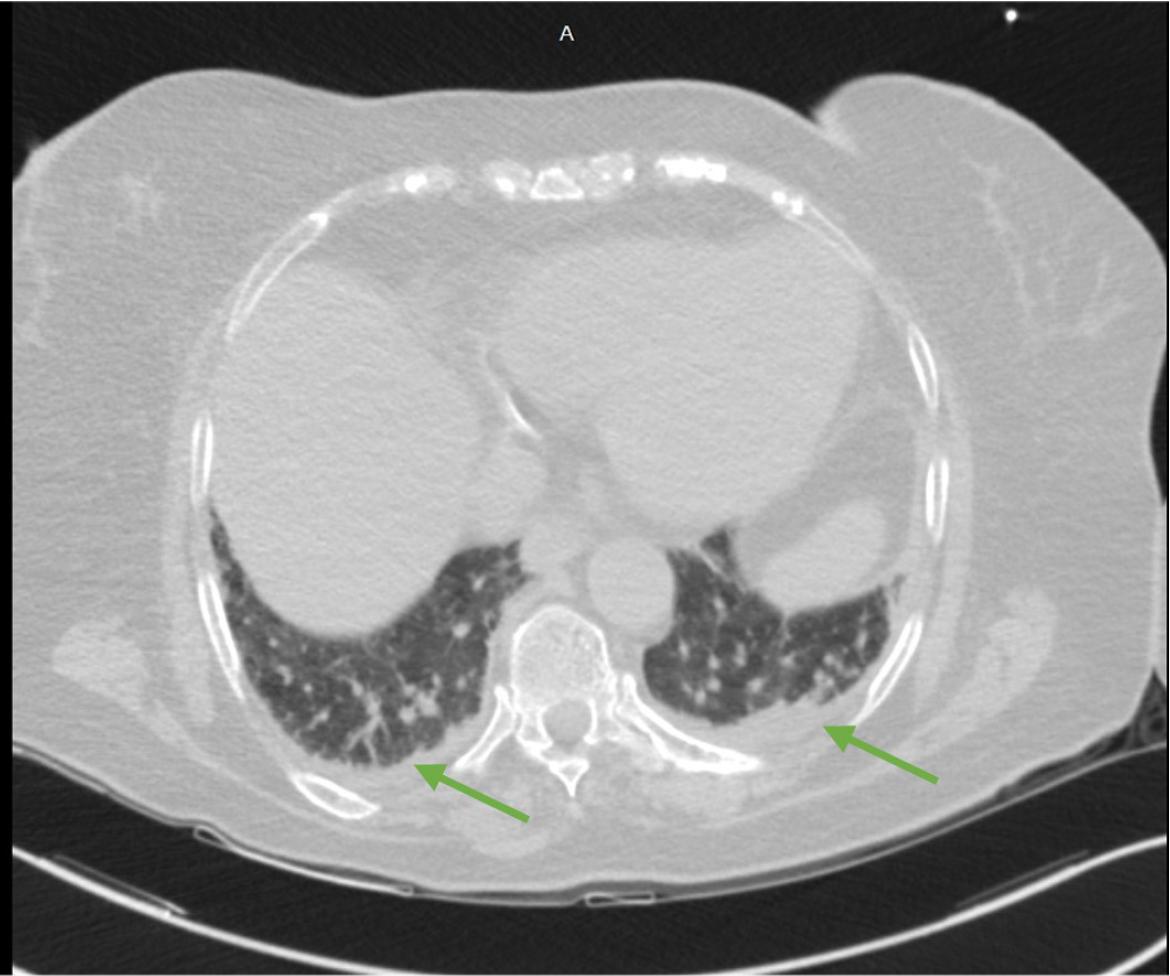

Computed tomography of the lung showing bilateral lower lobes consolidations. The arrows indicate subsegmental lower lobes consolidation with minimal pleural effusion.